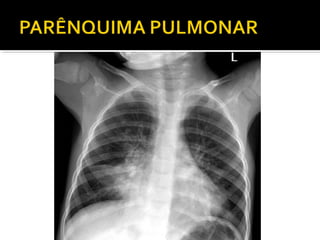

Este documento fornece parâmetros técnicos para realizar uma radiografia de tórax, incluindo posicionamento correto do paciente, dose adequada de radiação e estruturas anatômicas a serem avaliadas, como coração, pulmões, pleura, diafragma e ossos do tórax.